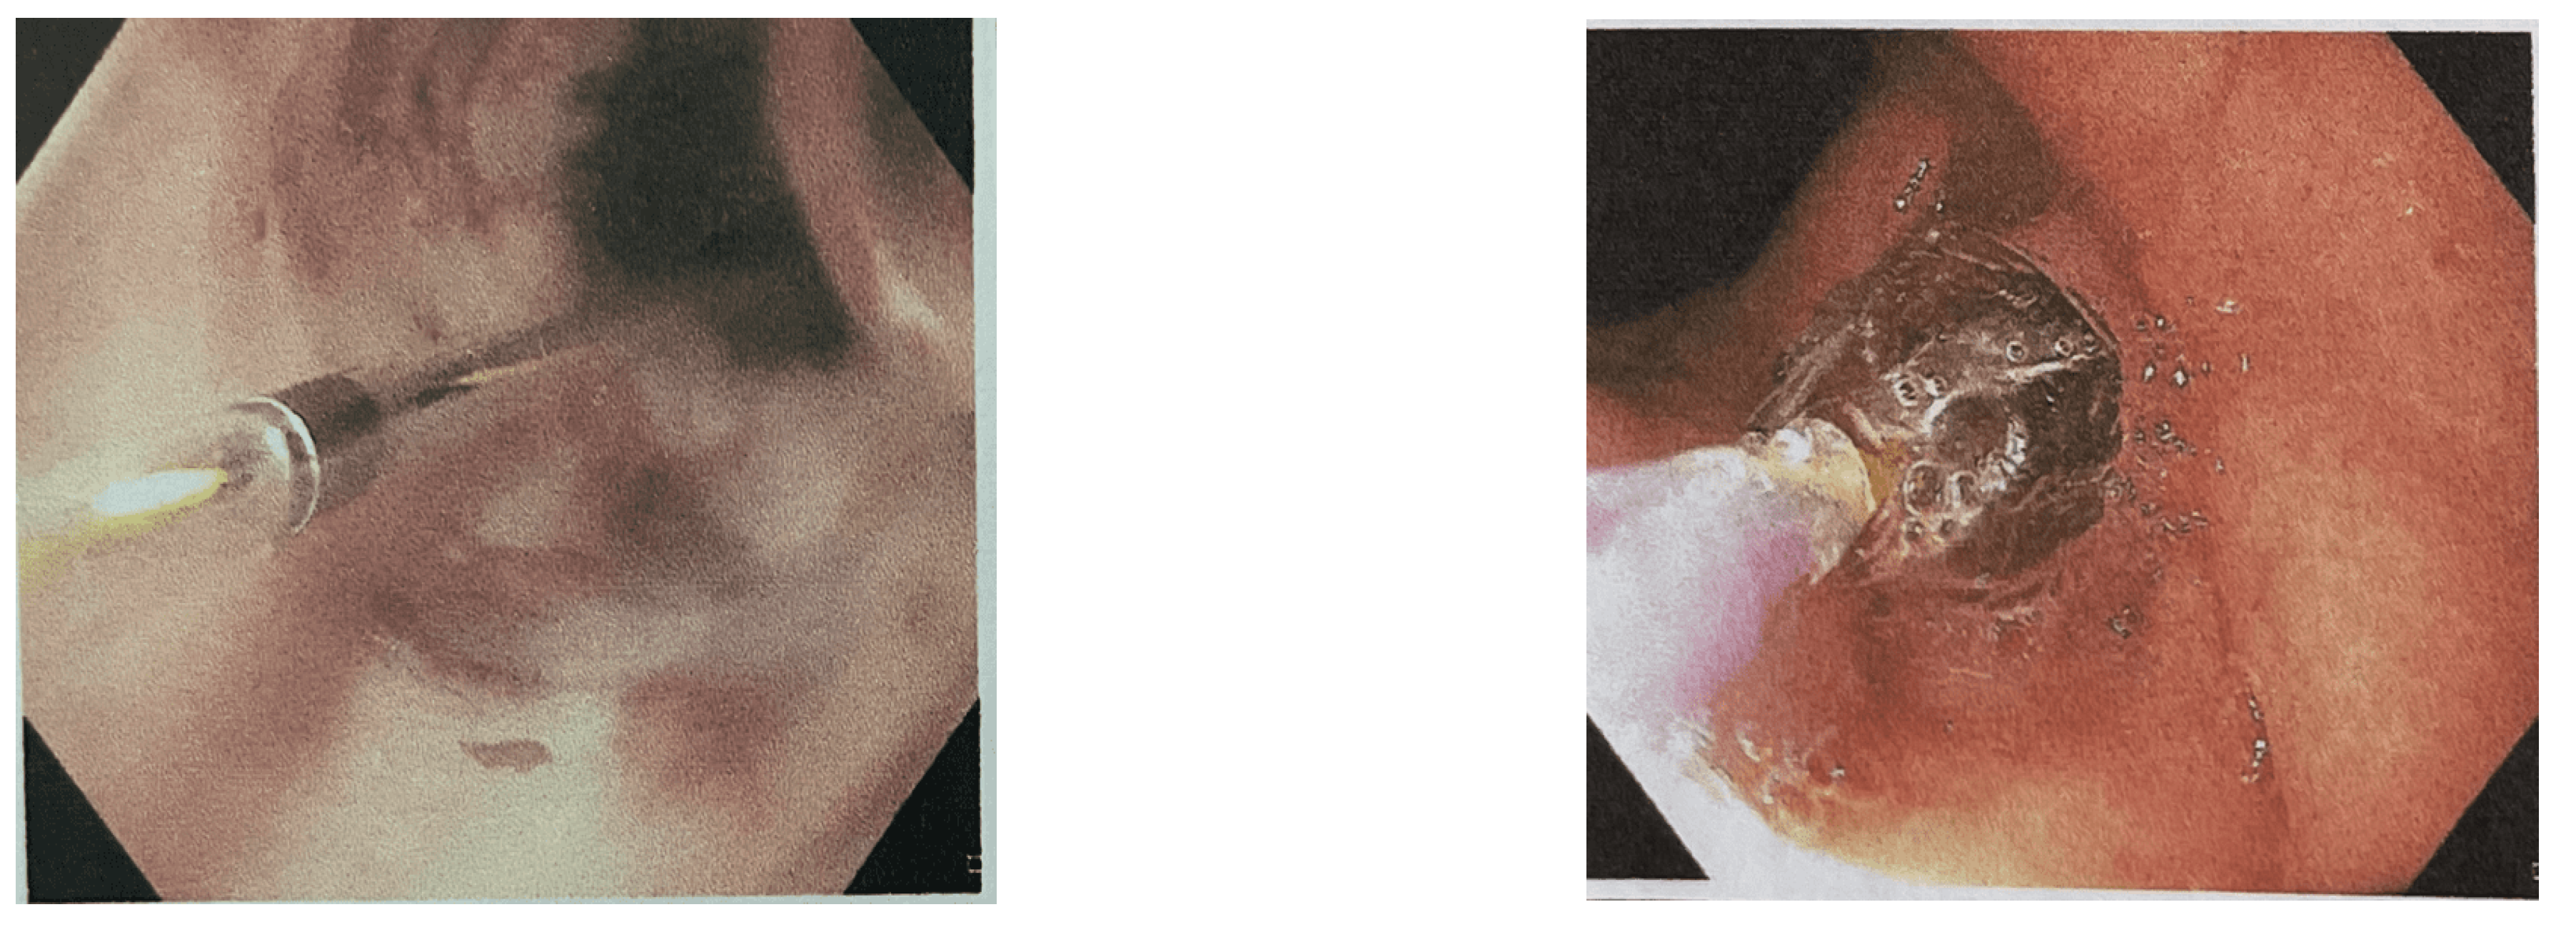

Figure 2. Pyloric stricture with TTS balloon in place.

3.3. Pyloric Strictures

Most of pyloric stricture were complex and tight stricture. Pyloric stricture (alone or combined with esophageal stricture) resulted lower successful rate (50%) than esophageal dilatation (66.7%) (Figure 2).

Overall successful, recurrent and refractory rate were 62.5%, 25% and 12.5% respectively (Table 2).